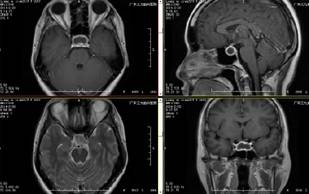

辅助检查:门诊脑脊液常规及生化未见异常;MRI平扫+增强示:1.鞍区囊性占位性病变,考虑垂体脓肿可能。行血常规、心功六项、凝血三项、肝功能、肾功能、传染病八项等均未见异常;内分泌:垂体催乳素(PRL)75.168ug/L。

诊断为:垂体脓肿。予抗感染治疗半月后复查颅脑MRI平扫+增强,提示病灶无明显改变,经家属同意。完善相关术前准备后于2月27日在全麻下行“经鼻蝶垂体脓肿切除术”,术中依据导航准确定位鞍底脓肿位置,切开脓肿壁可抽出量约5ml黄色脓液,双氧水清洗脓腔并开放脓肿腔引流,术程顺利,术后予止血、加强抗感染及营养支持等对症支持治疗;经治疗1周后头痛、发热症状消失,精神状况良好。